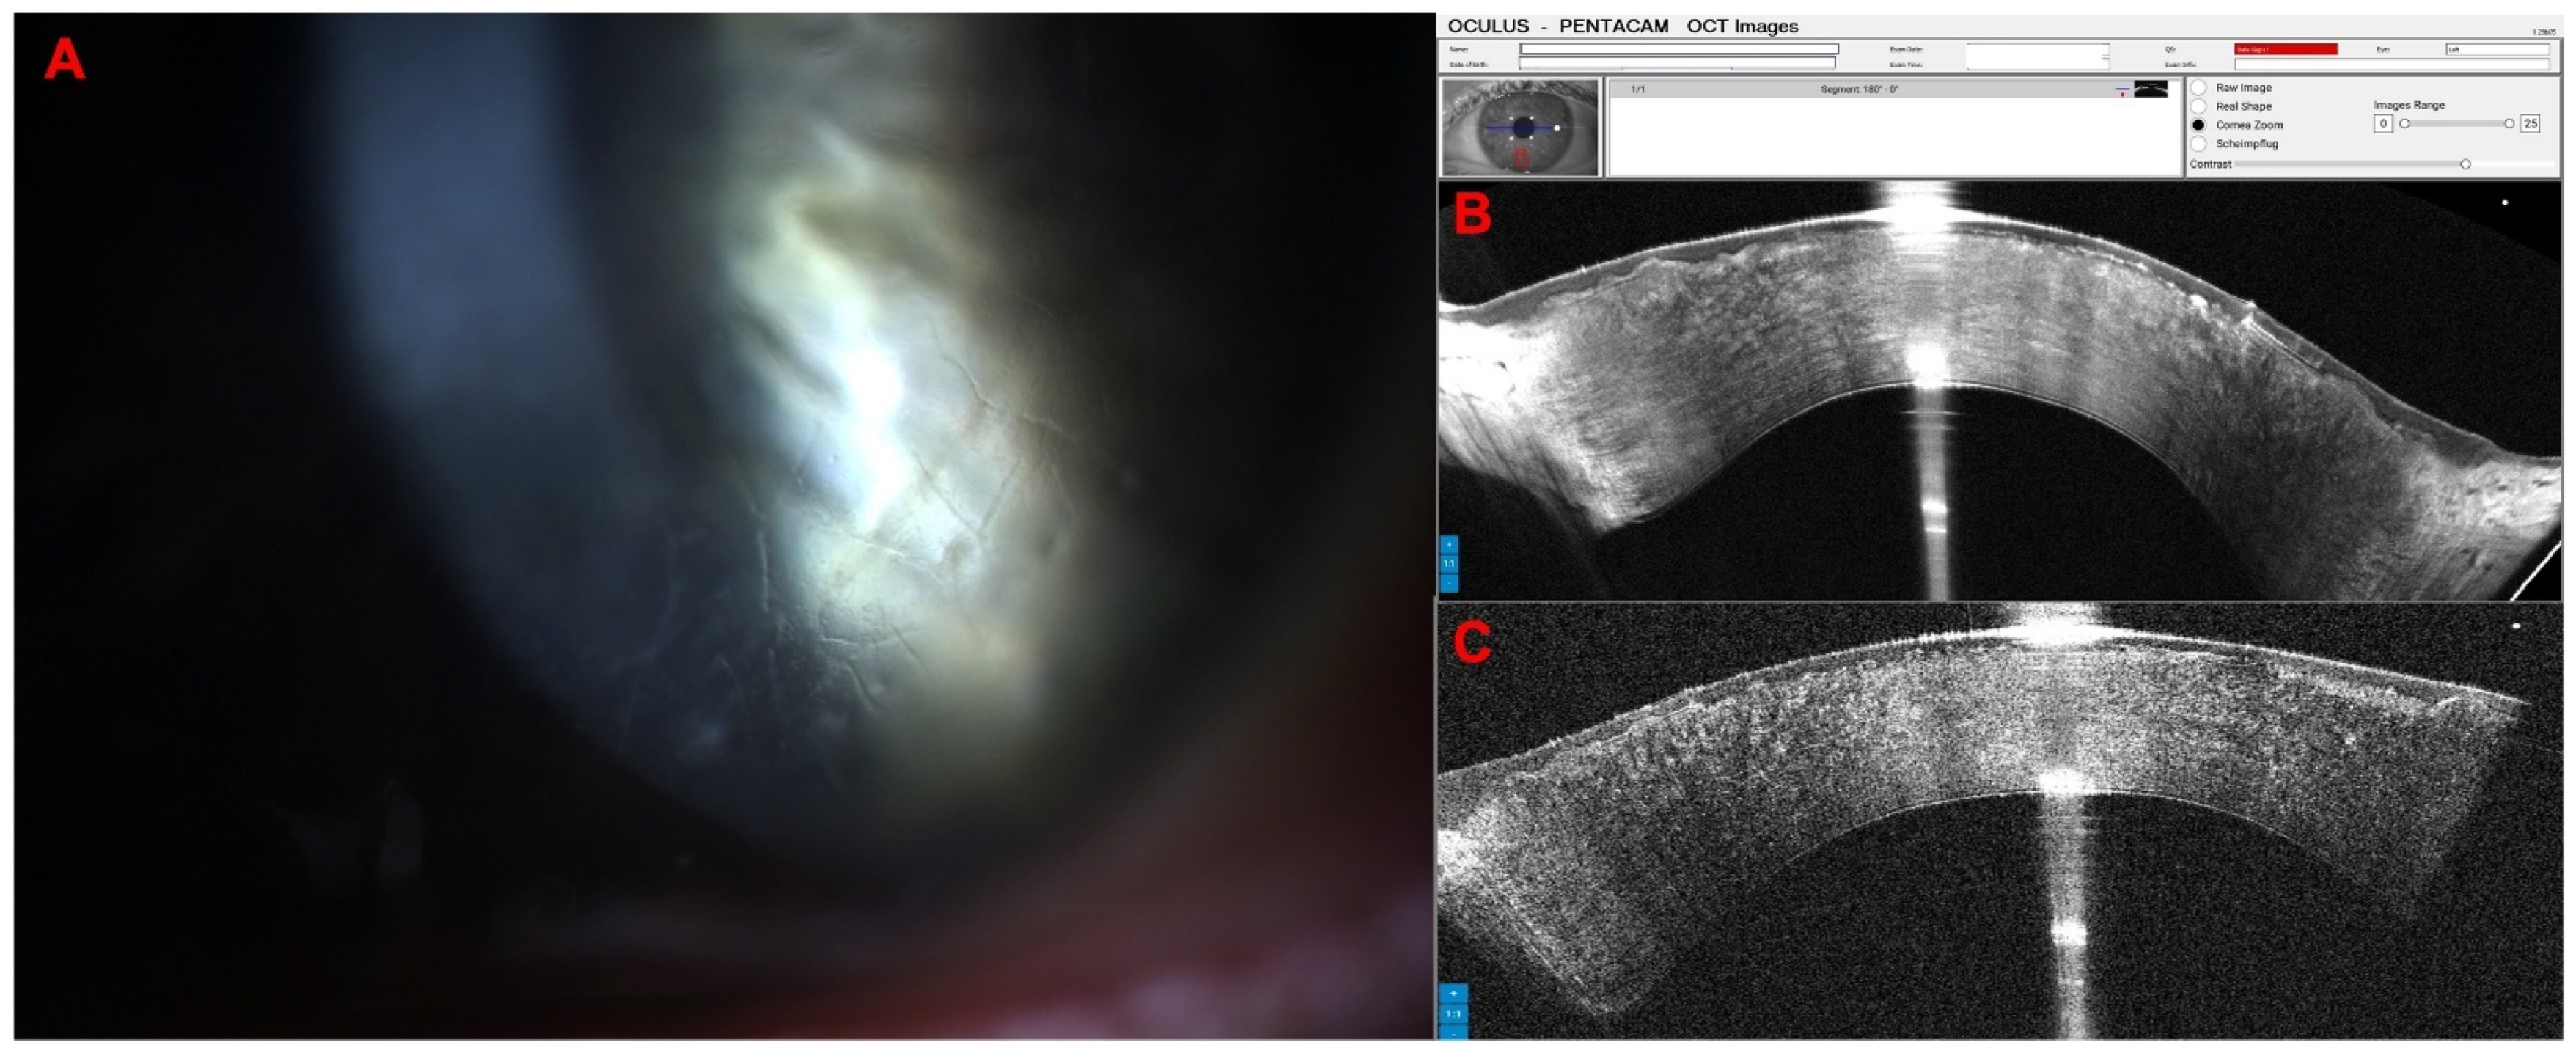

Combined Rotating Ultra-High-Resolution Spectral Domain OCT and Scheimpflug Imaging for In Vivo Corneal Optical Biopsy

1.3. The Pentacam® Cornea OCT

2. Materials and Methods

3. Results